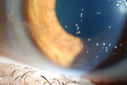

"Jelly Bumps" Soft Contact Lens1405 viewsYoung female patient comes in wearing overnight contact lenses. Complains of irritation in both eyes. Denies sleeping in SCL. Slit lamp exam shows little jelly bumps underneath the contact lens in both eyes. Was issued a new pair and lectured on handling them. 00000